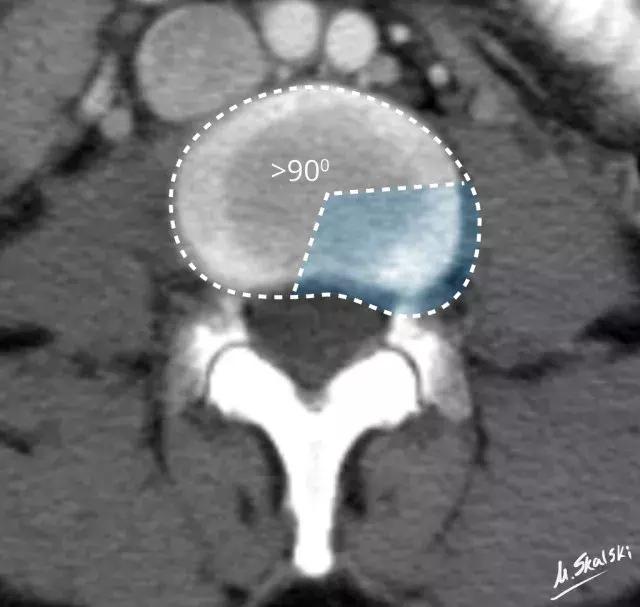

1. 椎间盘膨出(Disc bulge)

纤维环松弛但完整,髓核皱缩,表现为纤维环均匀超出椎体终板边缘。

图 3 椎间盘膨出的影像学定义为突出部分>椎间盘边缘的25%,或者突出的两边与髓核的中心的夹角>90